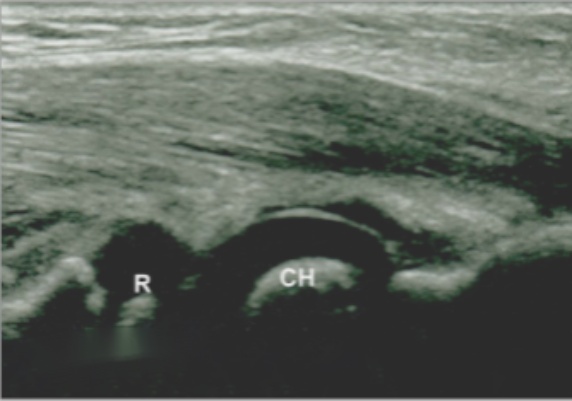

还可以在前臂旋后位肱桡关节外侧冠状位纵切面观察桡骨头和肱骨小头的位置关系。在正常儿童肘关节的超声图像上,可以见到两个圆形的低回声隆起,我们将其称为“双峰征”(见图2(a))。肱桡关节对线正确的第二个标志是桡骨(凹面)和肱骨(凸面)的相应关节面处于同一平面上(见图2(b)箭头处),我们将其称为“一致性[9]”。在肱桡关节外侧冠状位纵切面的异常声像中,桡骨头与肱骨的正常位置关系丢失,两种征象均不可见(见图2(c)),此可作为环状韧带卡压进入肱桡关节的提示。

(a) (b) (c)

Figure 2. Sonographic findings of the lateral coronal longitudinal section

2. 外侧冠状位纵切面超声表现